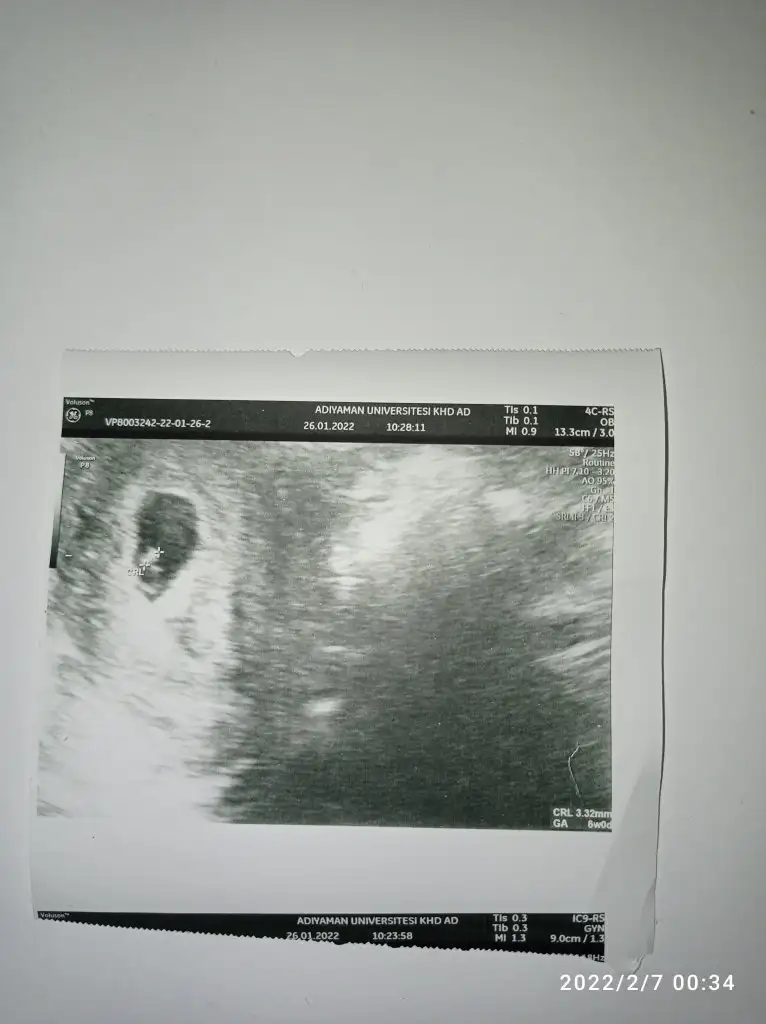

Evet benim o bebeğimi kaybettim malesefMerhaba tekrar burdaki ultrason da size ait değil mi bu usg 26 ocağa ait